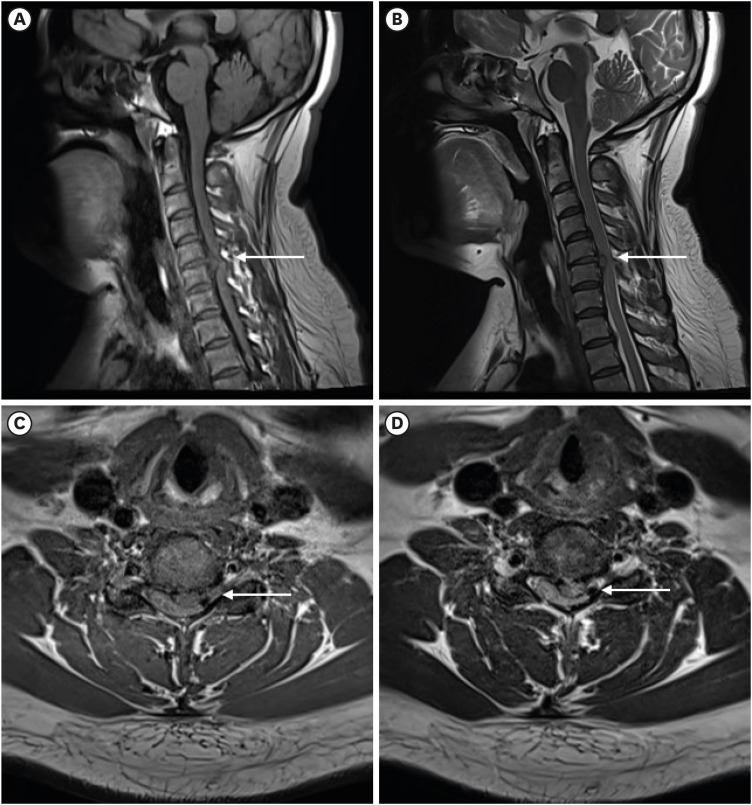

Intradiscal electrothermal therapy (IDET) is a minimally invasive procedure that alleviates chronic discogenic pain by delivering controlled heat to modify collagen and destroy pain-conducting nerve endings. While IDET offers a less invasive alternative to surgery, it carries risks such as nerve damage, infection, vertebral osteonecrosis, and, rarely, spinal cord injury. This report presents the case of a 36-year-old woman who developed left-sided hemiparesis following IDET for cervical disc herniation at the C5/6 level. Magnetic resonance imaging revealed cervical cord edema, and examination revealed neurological deficits, including reduced proprioception, motor strength, and senses of pain and temperature. Anterior cervical discectomy and fusion led to thermal injury on the left ventral spinal cord, and postoperative recovery resulted in significant neurological improvement, although some sensory deficits persisted. This case underscores the importance of appropriate patient selection and meticulous procedural technique to prevent severe complications, emphasizing the importance to reserve IDET for specific cases and to consider alternatives for more complex spinal conditions.